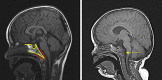

"CHARGE syndrome" is a complex syndrome with high and extremely variable comorbidity. As a result, clinicians may struggle to provide accurate and comprehensive care, and this has led to the publication of several clinical surveillance guidelines and recommendations for CHARGE syndrome, based on both single case observations and cohort studies. Here we perform a structured literature review to examine all the existing advice. Our findings provide additional support for the validity of the recently published Trider checklist. We also identified a gap in literature when reviewing all guidelines and recommendations, and we propose a guideline for neuroradiological evaluation of patients with CHARGE syndrome. This is of importance, as patients with CHARGE are at risk for peri-anesthetic complications, making recurrent imaging procedures under anesthesia a particular risk in clinical practice. However, comprehensive cranial imaging is also of tremendous value for timely diagnosis, proper treatment of symptoms and for further research into CHARGE syndrome. We hope the guideline for neuroradiological evaluation will help clinicians provide efficient and comprehensive care for individuals with CHARGE syndrome.